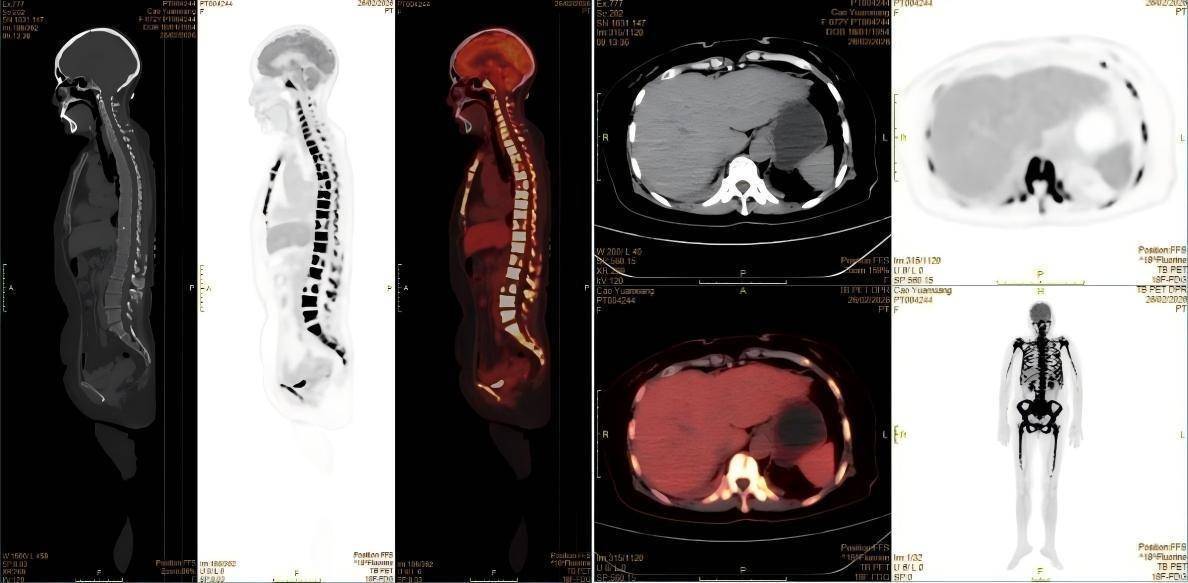

经PET-CT检查,患者全身骨弥漫性明显代谢增高,其他脏器均并未找到明确的实体原发灶,这样的显像结果推翻了肿瘤骨转移的初步诊断。核医学科医生看到这样的显像结果,并结合患者的临床表现,一个新的诊断方向在脑海中回荡:淋巴瘤?血液系统疾病?按照这一方向,为患者进一步进行了骨髓穿刺等检查,终于这个凶手被找到——急性淋巴细胞白血病。

△患者PET-CT的显像图

急性淋巴细胞白血病是一种起源于淋巴细胞的恶性肿瘤,其异常增生的白血病细胞会浸润全身骨骼和骨髓,破坏骨代谢平衡,导致骨骼出现弥漫性代谢活跃和浓聚表现。这正是患者在PET-CT和骨扫描上出现异常浓聚的原因。同时,患者持续发热、体重骤降等症状,也是白血病细胞大量增殖、释放致热原并抑制机体正常免疫功能的典型表现。